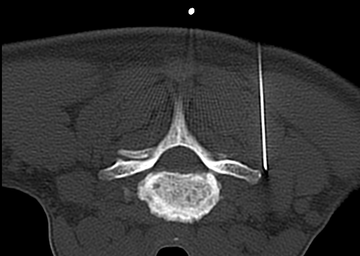

Periradikuläre Therapie

Die Periradikuläre Therapie (PRT) ist die bildgeführte, perkutane Applikation von Medikamenten direkt an einer Nervenwurzel kurz nach ihrem Austritt aus dem Wirbelsäulenkanal. Es gibt 2 Gründe um diese Therapie durchzuführen: Zum einem die sogenannte „therapeutische PRT“ zur Linderung von Schmerzen, die als Folge einer Kompression oder Reizung einer Nervenwurzel auftreten. Zum anderen die „diagnostische PRT“, deren Ziel es ist, bei unklarer Zuordnung der Beschwerden, beispielsweise infolge von Bandscheibenvorwölbungen in mehreren Etagen, die Höhe zu identifizieren, deren operative Entlastung am ehesten zur Schmerzfreiheit führt. Bei neurologischen Ausfällen ist die PRT jedoch auf keinen Fall ein Ersatz für eine operative Entlastung der geschädigten Nervenwurzel.

Auf dem Beispielbild ist die genaue Position der dünnen Nadel im Bereich des Austrittspunktes eines Nerven im Bereich der Halswirbelsäule zu erkennen.